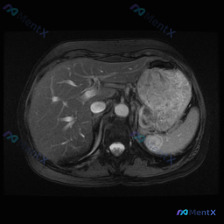

预设前提是“观察脾脏病变”,但拿到的单幅腹部MRI T2加权轴位图像分析结果明确显示:

- 肝脏、胆囊、胃腔、腹膜后大血管等结构均未见明确异常;

- 脾脏:大小形态大致正常,实质信号均匀,未见明显的异常高或低信号灶。

简单说:在这个层面、这个序列上,没有发现符合定义的“脾脏局灶性病变”。

📋答案:基于当前提供的单幅T2加权轴位图像,无法识别任何脾脏占位性病变;所谓“病变”极可能为正常解剖误判、伪影干扰、层面/序列局限所致。